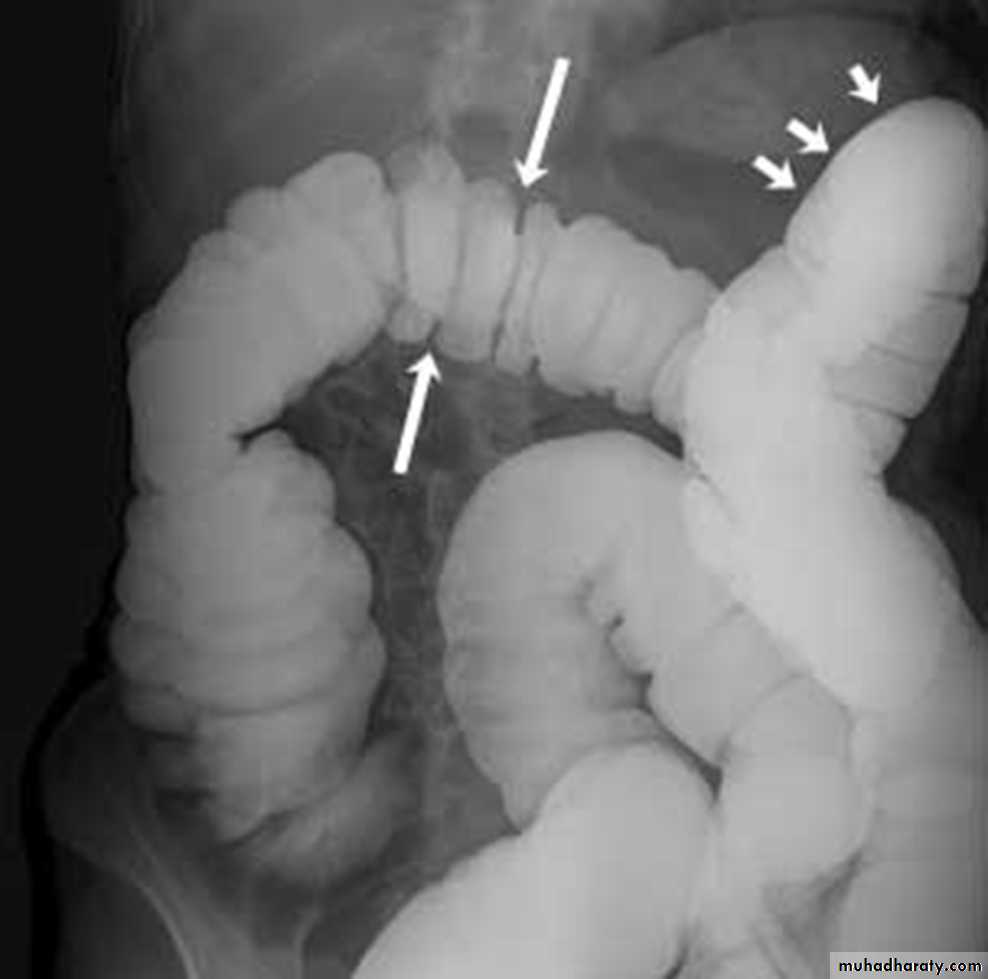

Radiological features of UC :

• Plain film : non specific ,may show marked dilatation of colon due to acute toxic dilatation ( fulminating case ), mural thickening with thumb printing in more sever cases Ba. Enema : usually double contrast allow for detail of colonic mucosa and contra-indicated in toxic dilatation due to the risk of perforation :1)- Widening of pre-sacral space ( Lat. View ).2)-The mucosal ulcers are undermined (Button _shaped ulcer) when most of the mucosa has been lost , island of mucosa remian giveing it ( a pseudo polyp) apperance .3)- Loss of haustration .4)- Narrowing of the colon , in early stage due to spasm , later on due to fibrosis .

• 5)- Shortening of the colon due to fibrosis 6)- In late stage combination of (3 ,4 ,and 5) give rise to Lead pipe appearance .7)- Cobble – stone mucosa due to pseudo-polyposis .8)- Constant narrowing not relieved by relaxant indicate either stricture or malignant changes.

• Mucosal inflammation lends a granular appearance to the surface of the bowel. As inflammation increases , the bowel wall and haustra thicken.

• Mucosal ulcers are undermined (button-shaped ulcers). When most of the mucosa has been lost, islands of mucosa remain giving it a pseudo-polyp appearance.

• In chronic cases the bowel becomes featureless with loss of normal haustral markings, luminal narrowing and bowel shortening (lead pipe sign).